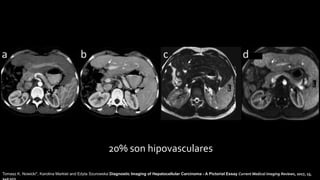

20% son hipovasculares